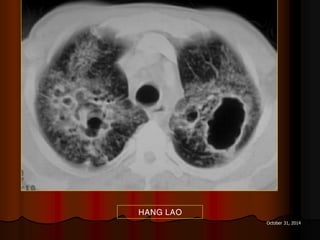

HANG LAO

Cavitating squamous cell carcinoma: hang lệch tâm, thành hang dày

Female: cavitary lesions, metastatic squamous cell carcinoma (cervix).

Mỗi hang thường có một banh nấm

Mukesh G. Harisinghani, MD et al. Tuberculosis from Head to Toe. Radiographics.

2000;20:449-470.

ASPERGILLOME

DẤU HIỆU LỤC LẠC

 Sign of tintinnabulum = Signe de grelot.

 Nấm Aspergillus có thể gây bệnh ở người với 2 thể chính:

 Thể xâm lấn mạch máu (Angioinvasive Aspergillosis): tổn

thương lan toả, gặp ở người có cơ địa suy giảm miễn dịch. Ở

thể này ta có dấu hiệu vầng hào quang (halo sign) trên CT.

 Thể banh nấm (Saprophytic Aspergillosis = Aspergilloma):

hình thành banh nấm (fungus ball) trong lòng các tổn thương

hang ở phổi, thường gặp ở BN có hang lao. Thể này cho dấu

hiệu lục lạc (Tintinnabulum sign) hay dấu hiệu liềm khí (Air

crescent sign) tuỳ theo tác giả.